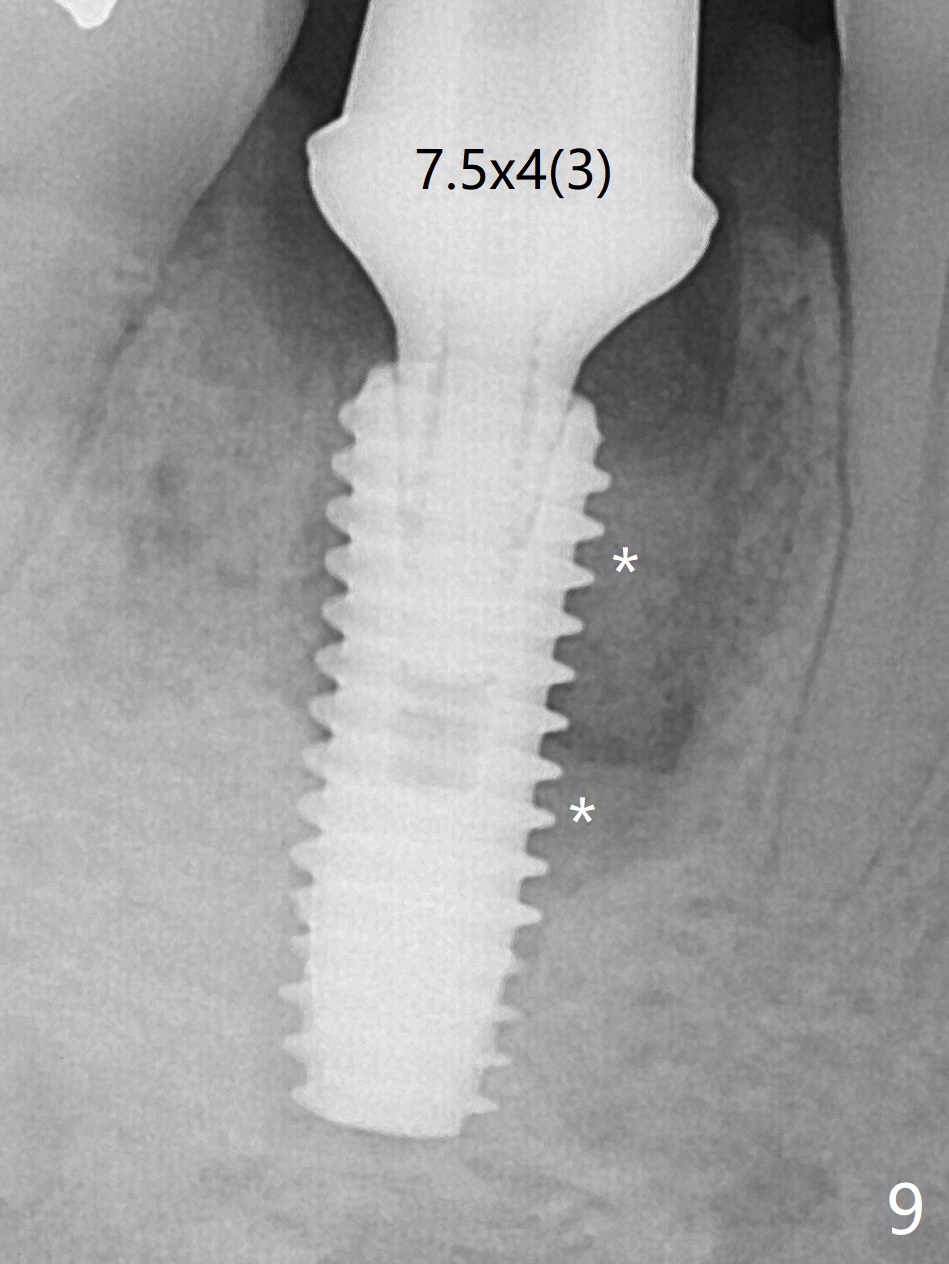

Preop oral Amoxicillin seems to be associated with reduction in the buccal and lingual (Fig.3 arrow) fistulae at #30, but there is mesiobuccal swelling (Fig.1 *) with 7 mm pocket (Fig.2). Osteotomy is initiated in the middle of the septum (Fig.3-5 S). As the osteotomy increases, it shifts mesially (Fig.6 arrow). Guided surgery is able to reduce shifting. A 5x13 mm implant is not seated completely (Fig.7) apparently due to osteotomy shifting. After removal of the bone from the osteotomy distally, the implant remains unseated with lower torque value (Fig.8). Following reuse of the 4.3 mm drill deeper by 1-2 mm, the implant is seated to a satisfactory depth (Fig.9 with increase in torque to 50 Ncm) with placement of Vera Graft (*) and a 7.5x4(3) mm abutment. After a second round of allograft placement (Fig.10 *), the implant is found to be 4 mm from the IAC. At the later stage of osteotomy, the coronal end of the septum is destroyed with loss of osteotomy depth landmark. It is apparent that the soft tissue landmark may be more reliable. The implant threads appear to be covered by the bone graft 3.5 months postop (Fig.11). The abutment is changed to 6.5x5(3) mm one before impression with minor margin prep. The bone density seems to increase 5 months postop, i.e., immediately post cementation (Fig.12) and 10 months postop (5 months post cementation (after retightening abutment), Fig.13 (*)). Periimplantitis develops mesiobuccally, consistent with bone loss 1 year 7 months post cementation (Fig.14 *); the implant seems to have been buccally placed. Bone graft is necessary with PRF or GEM21S if the vein is small and 6-month membrane with a hole around a 7.5x4(4) cemented abutment for easy wound closure. Take 5x5 CM CBCT to determine which wall has defect, buccal or lingual. Check mesial contact. If so, remove the crown, reseat the abutment (possible incomplete seating) and re-impress after bone graft.